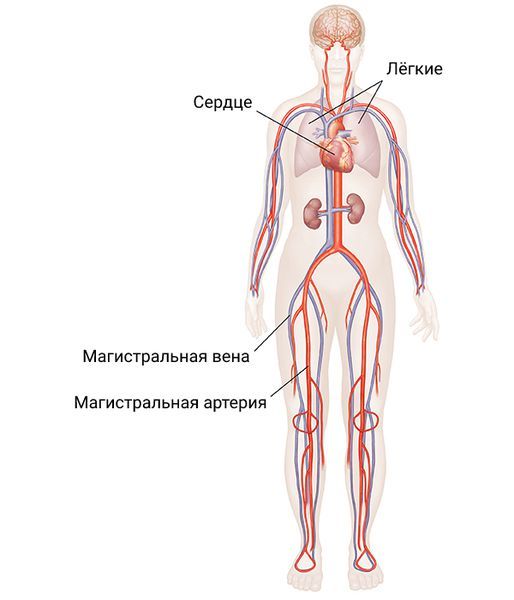

По литературным данным, травмы крупных сосудов в мирное время составляют пятую часть случаев от всех неотложных патологий сосудов и чуть меньше 1,5% различных видов механической травмы [2]. При этом на долю сочетанного повреждения магистральных сосудов и других органов приходится до 81,8 % травм [3]. При повреждении магистральных сосудов шеи смертность достигает 40 %, а стойкие неврологические последствия отмечаются у 80 % пациентов [4].

Магистральные сосуды